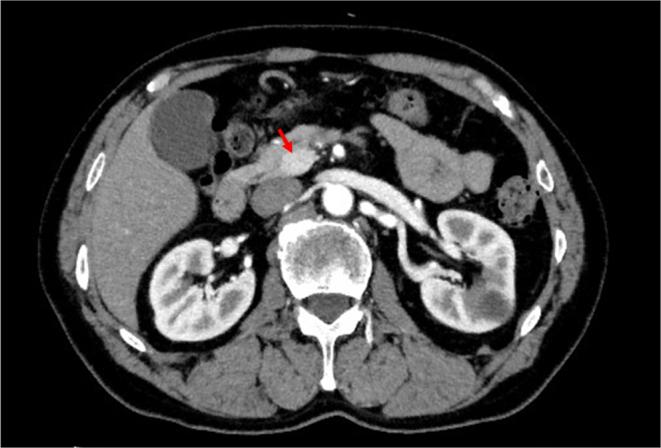

Unawareness of postprandial hypoglycemia for 5 years was identified in a 66-year-old man at a local clinic. The patient was referred to our hospital because of this first awareness of hypoglycemia (i.e. lightheadedness and impaired consciousness) developing after lunch. In a 75 g oral glucose tolerance test, the plasma glucose concentration was decreased to 32 mg/dL (1.8 mmol/L) at 150 min with relatively high concentrations of insulin (8.1 μU/mL), proinsulin (70.3 pmol/L), and C-peptide (4.63 ng/mL). In a prolonged fasting test, the plasma glucose concentration was decreased to 43 mg/dL (2.4 mmol/L) at 66 h with an insulin concentration of 1.4 μU/mL and a C-peptide concentration of 0.49 ng/mL. Computed tomography showed an 18 mm hyperenhancing tumor in the uncinate process of the pancreas. A selective arterial calcium stimulation test showed an elevated serum insulin concentration in the superior mesenteric artery. The patient was then diagnosed with insulinoma and received pancreaticoduodenectomy. Continuous glucose monitoring (CGM) using the Dexcom G6 system showed unawareness of hypoglycemia mainly during the daytime before surgery. When the sensor glucose value was reduced to 55 mg/dL (3.1 mmol/L), the Dexcom G6 system emitted an urgent low glucose alarm to the patient four times for 10 days. Two months after surgery, an overall increase in daily blood glucose concentrations and resolution of hypoglycemia were shown by CGM. We report a case of insulinoma with unawareness of postprandial hypoglycemia in the patient. The Dexcom G6 system was helpful for assessing preoperative hypoglycemia and for evaluating outcomes of treatment by surgery.

一名66岁男性在当地诊所被发现5年来一直未意识到餐后低血糖。该患者因午餐后首次出现低血糖意识(即头晕和意识障碍)而被转诊至我院。在75克口服葡萄糖耐量试验中,150分钟时血浆葡萄糖浓度降至32毫克/分升(1.8毫摩尔/升),同时胰岛素(8.1微单位/毫升)、胰岛素原(70.3皮摩尔/升)和C肽(4.63纳克/毫升)浓度相对较高。在延长禁食试验中,66小时时血浆葡萄糖浓度降至43毫克/分升(2.4毫摩尔/升),胰岛素浓度为1.4微单位/毫升,C肽浓度为0.49纳克/毫升。计算机断层扫描显示胰腺钩突部有一个18毫米的强化肿瘤。选择性动脉钙刺激试验显示肠系膜上动脉血清胰岛素浓度升高。该患者随后被诊断为胰岛素瘤并接受了胰十二指肠切除术。使用德康G6系统进行的连续血糖监测(CGM)显示,术前主要在白天存在低血糖未被察觉的情况。当传感器葡萄糖值降至55毫克/分升(3.1毫摩尔/升)时,德康G6系统在10天内四次向患者发出紧急低血糖警报。术后两个月,CGM显示每日血糖浓度总体升高,低血糖症状消失。我们报告了一例患者患有胰岛素瘤且未意识到餐后低血糖的病例。德康G6系统有助于评估术前低血糖情况以及评估手术治疗效果。